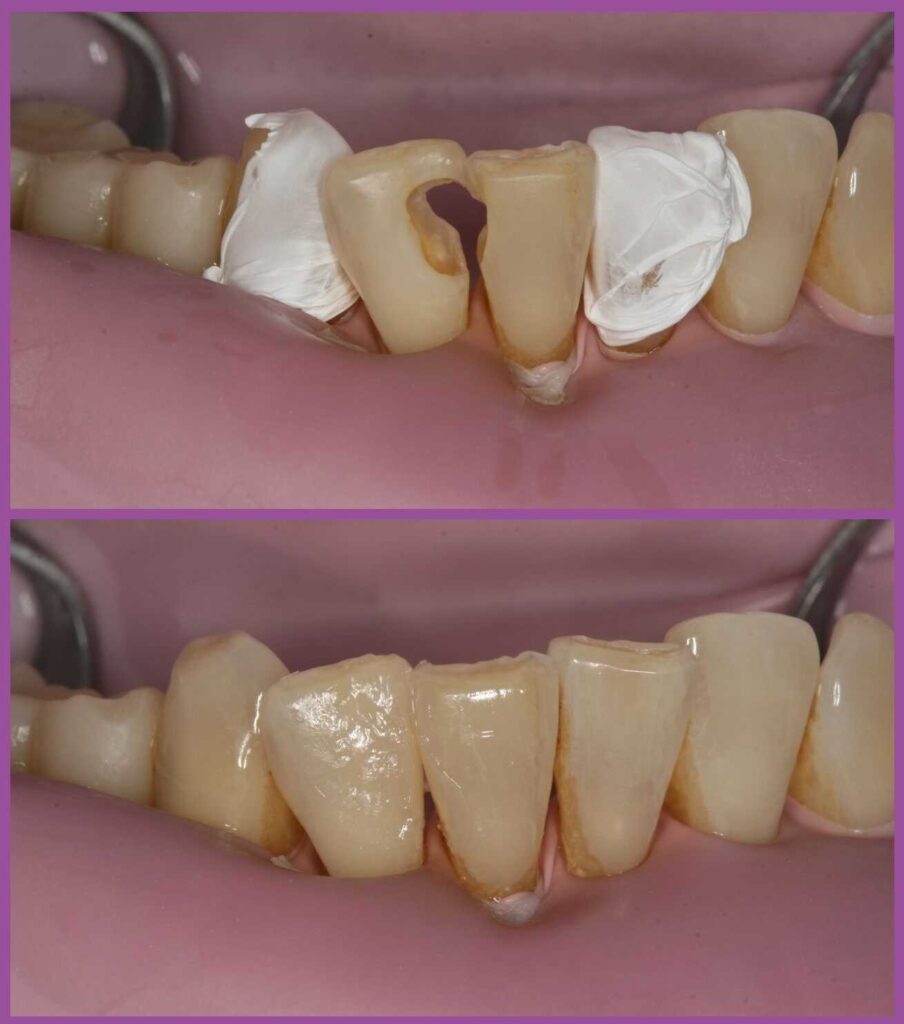

A modern kompozittömés, amelyet a páciensek gyakran csak láthatatlan fogtömésként emlegetnek, olyan szépen belesimul a fogba, hogy még a szakértő szemnek is nehézséget okoz a felfedezése. A láthatatlan fogtömés azért „tűnik el”, mert a fogorvos a tömés során helyreállítja a fog anatómiáját.

A modern kompozittöméseket úgy építjük fel, hogy az kövesse a fog szerkezetét és eredeti formáját. A tömés színét természetesen a páciens fogszínéhez igazítjuk, így a végeredmény pontosan olyan lesz, mint az eredeti saját fog. Mivel a fog funkcionalitása a visszanyert eredeti anatómiával szépen helyrehozható, az eredmény tartósabb, mint a korábbi eljárásoké.

Ha összeveti a fenti képet az amalgámtöméseket felmutató fotóval, akkor két megdöbbentő felfedezést tehet. Az egyik az, hogy mind a két képen ugyanaz a fogsorrészlet látható. A másik, hogy mennyire „eltűntek” a tömések a második képen. Valóban, a modern kompozittömések esztétikai összhatása lenyűgöző!